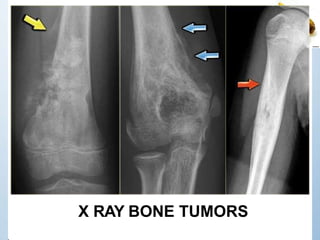

X RAY BONE TUMORS

– X-rays: can show the location, size, and

shape of a bone tumor. Chest x-rays are

performed to determine the presence of

lung metastasis